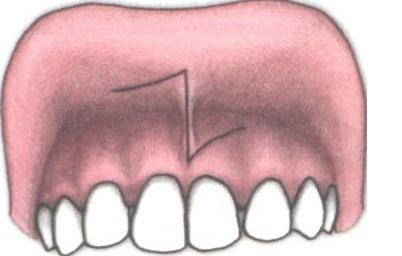

В нормальном положении уздечка вплетается в десну примерно на расстоянии 0,5-0,8 см от шеек передних резцов. При более низком креплении или когда уздечки губы заходит за передние резцы и точки крепления вообще не видно, ее считают короткой. В таких случаях она начинается в средней части верхней губы и прикреплена приблизительно на 0,4-0,6 см выше десны, в области щели между передними резцами (диастемы).

- Укороченная уздечка губы, а также ее близкое крепление к краю альвеолярного отростка становятся причиной оттягивания межзубных сосочков десны в пространстве между резцами. В результате в костной ткани между лунками зубов формируется щель – диастема. Кроме того, увеличивается расстояние между коронками.

- При наличии диастемы (щели) между центральными резцами. Вплетенная в межзубный сосочек и формирующая толстый тяж уздечка верхней губы не дает резцам сходиться к центру. К тому же воздействие небольшой постоянной нагрузки приводит к постепенному увеличению диастемы и смещению зубов вперед и в стороны от центра, а также развитию пародонтита вследствие постоянного травмирования межзубного сосочка.